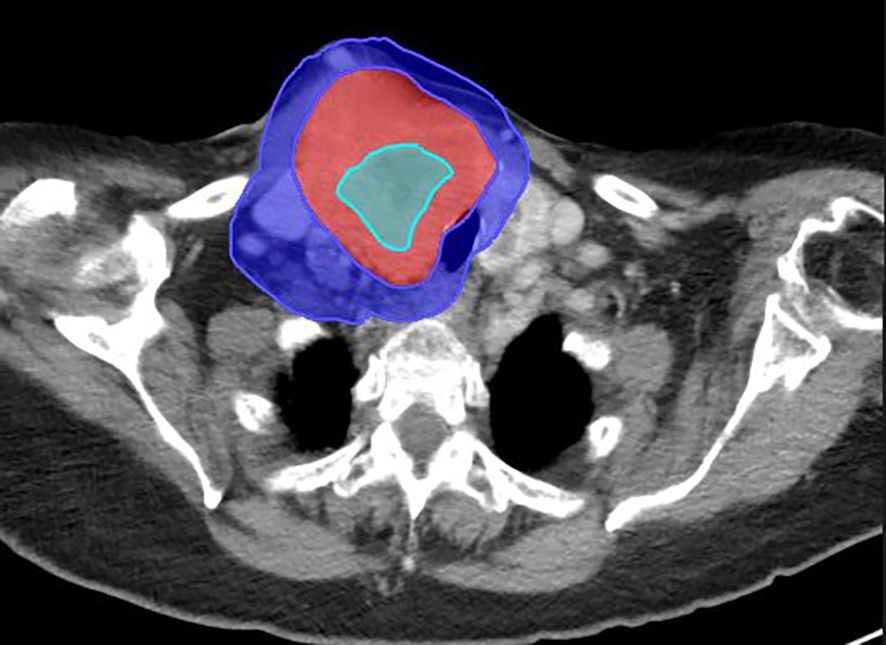

Early Experience with SBRT-based Partial Tumor irradiation targeting Hypoxic segment (SBRT-PATHY) of large bulky tumors.

Large bulky tumors possess poor prognostic characteristics that make tumor control difficult. SBRT-based Partial Tumor irradiation targeting Hypoxic segment (SBRT-PATHY) has been described as a spatially fractionated radiotherapy technique that induces both bystander and abscopal effects by sparing the peri-tumoral immune micro-environment thus minimizing the negative effects of radiation induced lymphopenia. The aim of these case reports is to present our early experience of 4 cases in the utilization of SBRT-PATHY at our institution.